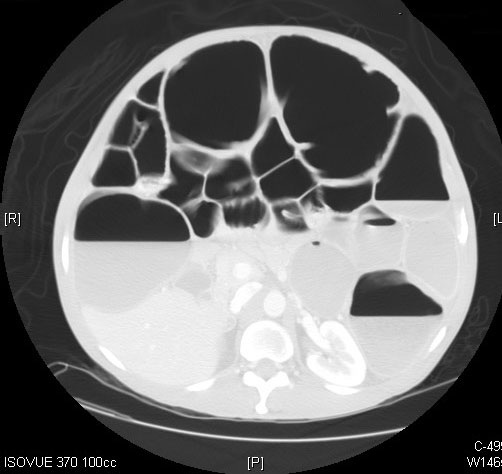

Computed tomography (CT) imaging of the abdomen and pelvis is a far more sensitive and specific tool in the assessment of LBO. (See Figures 1 and 2.) CT imaging offers significantly more information than an abdominal X-ray, including the location of the occlusion, the possible etiology of the LBO, and/or any complications from the LBO, such as perforation.1,5 CTs can localize obstructing lesions with a reported sensitivity of 96% and specificity of 97%, making them highly effective at identifying the transition point from healthy to affected bowel.2,6

Figure 2. Axial Plane of a Computed Tomography Scan of the Abdomen and Pelvis Demonstrating a Dilated Large Bowel with Air Fluid Levels |

Source: Image courtesy of J. Stephan Stapczynski, MD. |